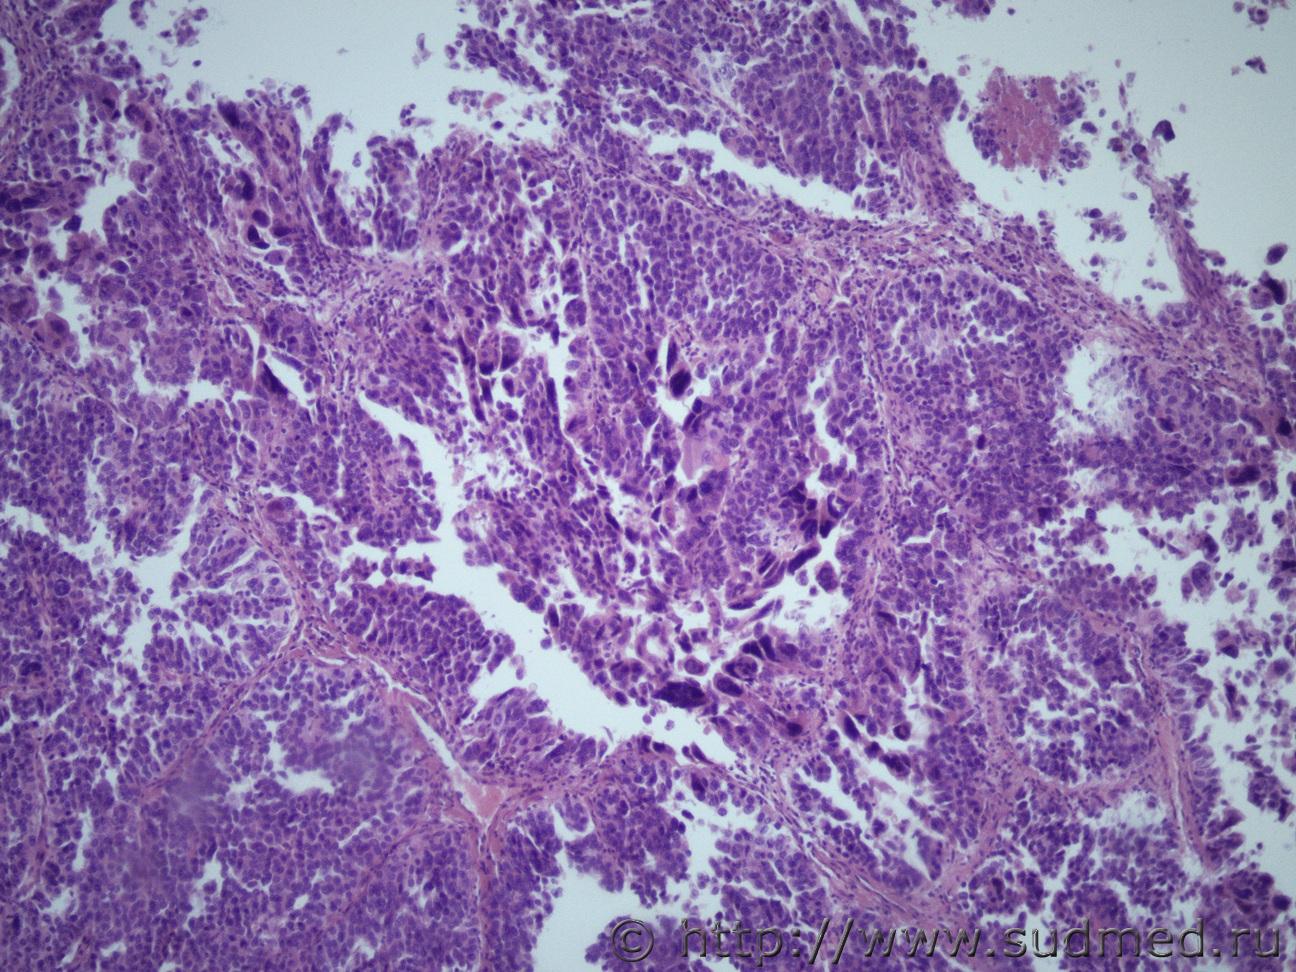

Ув. коллеги. Как и всегда необходима ваша профессиональная помощь. Жен 67 лет. На вскрытии - структура поджелудочной железы нарушена, гнойное распловление тела и хвоста пж, в области головки пж определяется плотноватый узел диаметром 5.5 см, богато васкуляризированный, на разрезе молочно-белого цвета с желтоватым оттенком, по консистенции близок к творожной массе. В области правой доли печени аналогичный узел. Судебная медицина - Прикрепленное изображение Судебная медицина - Прикрепленное изображениеСудебная медицина - Прикрепленное изображениеСудебная медицина - Прикрепленное изображениеСудебная медицина - Прикрепленное изображение

Метастатическая карциноидная ( нейроэндокринная)опухоль ( круглоклеточная монморфность с гиперхромными ядрами и некроз)

карциноидная ( нейроэндокринная)опухоль

Поддерживаю.